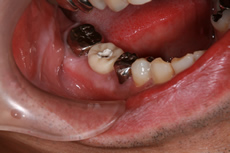

術前

術中